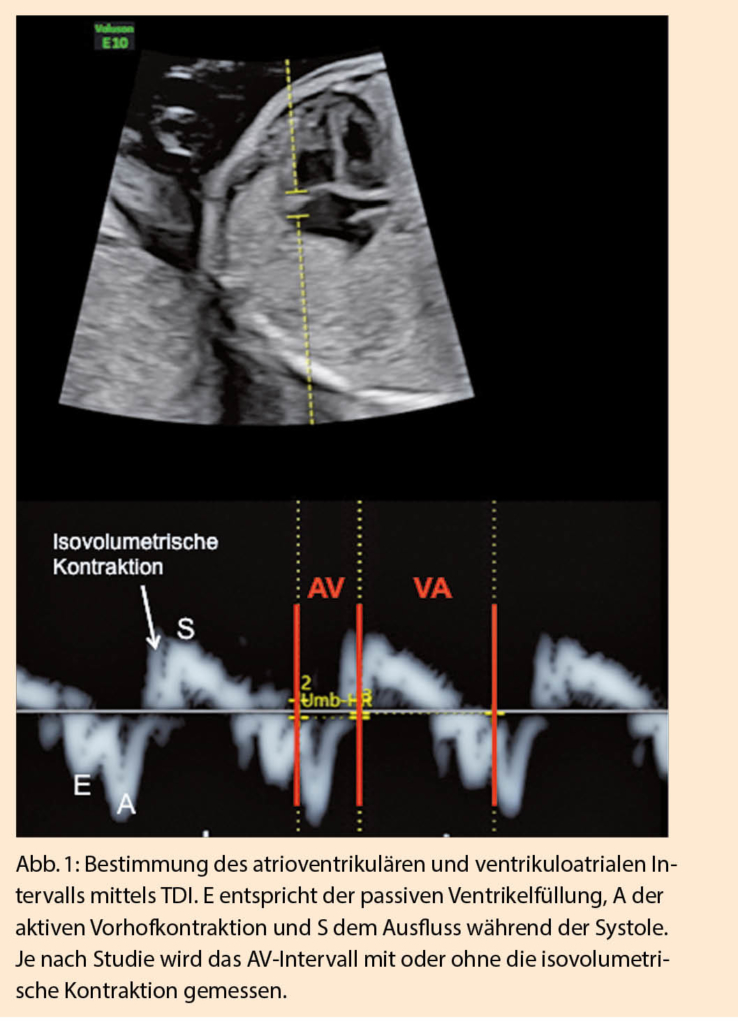

Bei fetalen Rhythmusstörungen unterscheidet man grundsätzlich zwischen Extrasystolen, Bradyarrhythmien und Tachyarrhythmien. Fetale Elektrokardiogramm (EKG)-Untersuchungen sind technisch schwierig durchzuführen und werden nur von wenigen Zentren angeboten. In der Beurteilung fetaler Rhythmusstörungen haben sich deshalb heute vor allem verschiedene Doppleruntersuchungen etabliert. M-Mode und Gewebedoppler (tissue Doppler imaging TDI) ermöglichen die Beurteilung von Vorhof- und Ventrikel-Wandbewegungen in zeitlicher Abhängigkeit (2); dies erlaubt die Messung des mechanischen atrioventrikulären Zeit-Intervalls, welches dem elektrischen PR-Intervall im EKG entspricht (Abb. 1) (3). Die simultane Aufzeichnung von Flussmustern in nahe beieinander liegenden Arterien-Venen Paaren mittels gepulstem Doppler bedient sich desselben Konzepts (3-6). Meist werden die Vena cava superior (VCS) und die aszendierende Aorta für diese Messung zugezogen, man kann aber auch die linke Vena brachiocephalica mit dem Aortenbogen oder die Arterie und Vena renalis kombinieren (7). Auch der Einfluss- und Ausflusstrakt im linken Ventrikel (LV in-out) kann zugezogen werden bei der gepulsten Dopplermessung (Abb. 2). Allen diesen Methoden ist eigen, dass die gemessenen AV-Überleitungszeiten in Relation stehen zur PR-Zeit, dieser jedoch nicht genau entsprechen. Dies konnte auch in postnatal durchgeführten Studien bestätigt werden, in denen eine simultane Aufzeichnung des EKGs möglich ist (8). Entsprechend ist es wichtig, sich je nach Wahl der Methode in der Interpretation an die entsprechenden Normwerte zu halten (9).